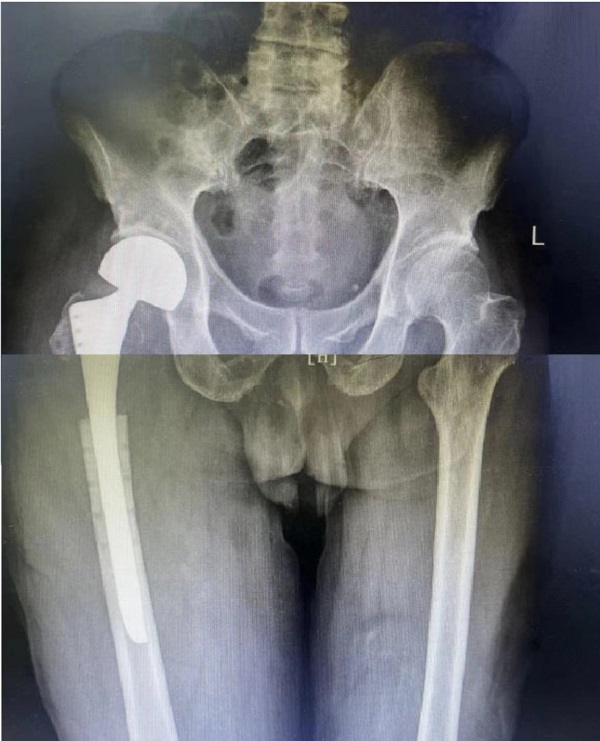

退休李師傅今年79歲,4個月前因右側股骨近端病理性骨折在外院行瘤體切除,鋼板內固定手術。近期下地活動時輕微扭傷后感右大腿根部疼痛伴活動受限,來二一五醫(yī)院拍片提示:右股骨近端骨折術后再骨折伴內固定斷裂。老年患者的股骨近端骨折若不積極正規(guī)治療,可能因長期臥床引起肺部感染、泌尿系感染、深靜脈血栓、褥瘡等并發(fā)癥,被稱為“人生的最后一次骨折”。

創(chuàng)傷骨科郭永良主任、王爭剛主任醫(yī)師仔細了解患者病史、查體閱片,和患者家屬多次溝通,闡明各種治療方案的優(yōu)缺點,最終決定行右股骨近端內固定鋼板及骨水泥取出、人工股骨頭置換術。手術由郭永良主任親自主刀、在王爭剛主任醫(yī)師等輔助下進行,歷時1.5小時順利完成?,F(xiàn)術后3周,患者髖關節(jié)功能恢復良好,可扶拐下地活動。